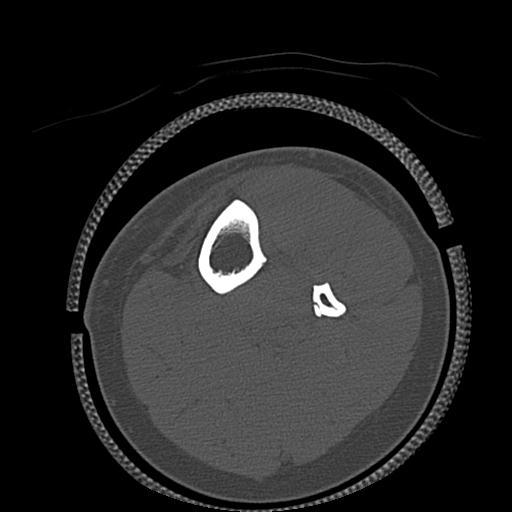

102755 1/4 2R 1/15 2R 右足関節 68歳女性 右三果脱臼骨折